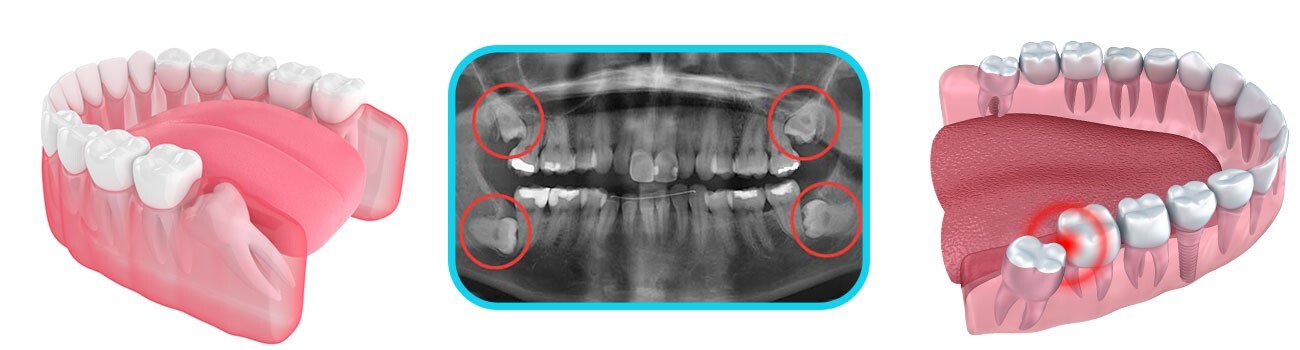

دندان عقل چیست؟

آخرین مجموعه دندان های بالغ به دندان عقل اختصاص داده می شود. در سنین ۱۷ تا ۲۵ سالگی دقیقاً در انتهای دندان آسیاب دوم روی فک بالا و پایین رویش خواهند کرد. بنابراین برخی از افراد جهت جلوگیری از درد و حتی عفونت و دیگر مشکلات لثه در صورت رشد دندان عقل، نیاز به کشیدن آن خواهند داشت.

به طور کلی می توان گفت عوارض نکشیدن دندان عقل طوری است که بهترین دندانپزشک شیراز بسیار توصیه خواهند کرد که دندان حتماً باید کشیده شود. چون فک انسان به اندازه ای بزرگ نیست که بتواند تمامی دندان ها را در خود جای دهد. به همین خاطر دندان عقل نیز به راحتی نمی تواند رشد کند. از این رو استخوان فک نیز دچار آسیب خواهد شد.